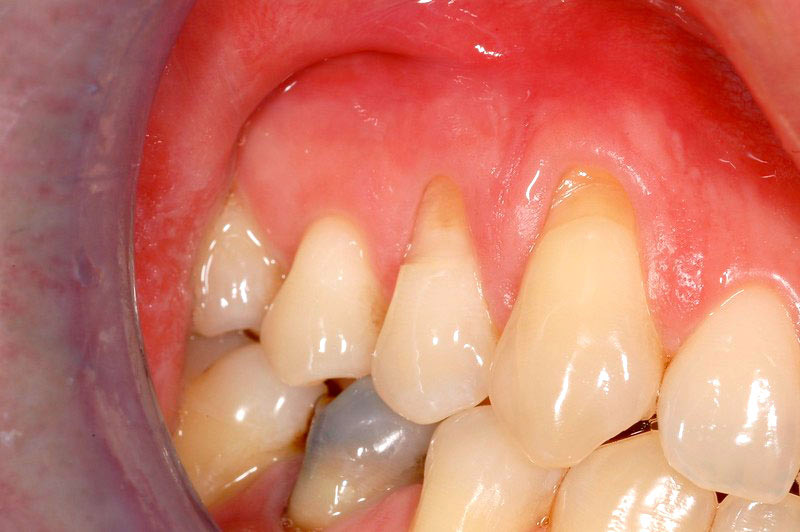

Situazione-parodontale-dopo-dell-intervento

Situazione parodontale dopo dell’intervento